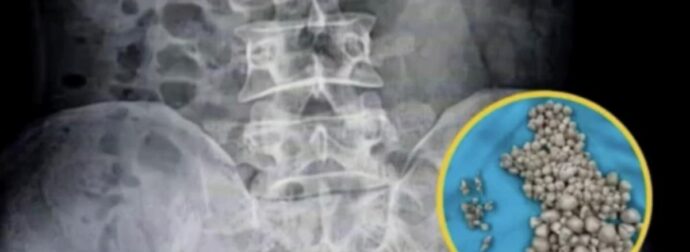

Οι γιατροί σοκαρίστηκαν αφού βρήκαν 300 πέτρες στα νεφρά σε νέα γυναίκα